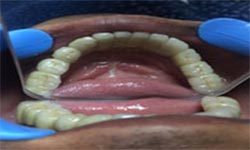

(9) Metal Ceramic Crowns

Before Treatment

After Treatment

Mr. Shiv Narayan Singh,aged 78yrs, came with a concern of multiple broken and mobile teeth with difficulty in chewing food. So, multiple RCTs followed by metal-ceramic crowns were delivered to the patient ,restoring his beautiful smile.